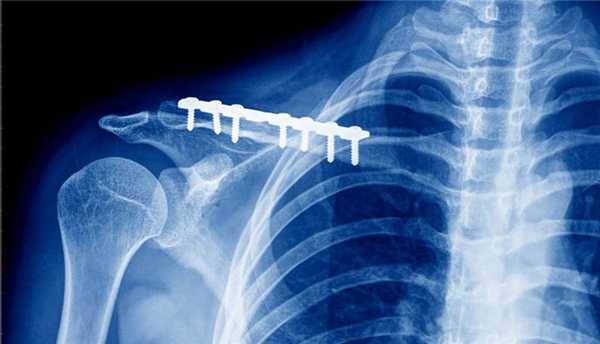

В первые несколько часов после перелома возможен остеосинтез - фиксация отломков кости с использованием специальных конструкций. Цель процесса - обеспечение неподвижности и создание условий для сращивания костей в правильном положении.

Если для сращивания перелома использовались винты, металлические пластины или другие фиксирующие конструкции, то после сращения их необходимо обязательно удалить. Причина в том, что инородные тела в организме могут спровоцировать образование кист и отторжение.

При помощи пластин можно фиксировать любую кость. Это удобный и надежный метод. Сегодня используют множество вариантов таких пластин, различающихся по размеру, форме, функциональности. Пластина используется при переломе голени и лодыжки, когда есть необходимость фиксации отломков кости. Ее удаление происходит в плановом порядке. Время проведения операции определяет врач.

С одной стороны удаление - это операция, но с другой - инородное тело может вызывать в организме нежелательные реакции. Конструкция устанавливается на время, в течение которого происходит сращивание костей. Факт сращения подтверждает рентгеновский снимок. Лечебная методика предусматривает удаление металлоконструкций после перелома, чтобы вероятность развития деформирующего остеоартроза была минимальной.